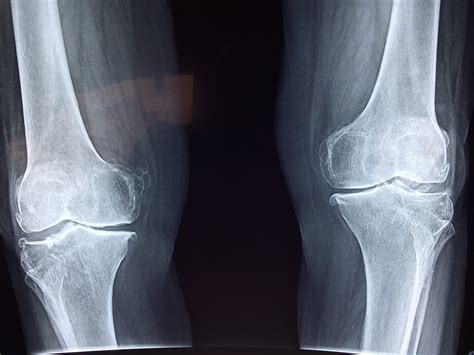

When you experience persistent knee pain, stiffness, or after a sudden injury, your primary care physician or orthopedist will often recommend imaging studies to determine the root cause. One of the first diagnostic tools utilized in clinical practice is a normal knee xray. While the term "normal" might sound dismissive if you are currently in pain, in the world of radiology, it is a crucial piece of information. It signifies that your bone structure, alignment, and joint space do not show immediate signs of fracture, severe dislocation, or advanced degenerative disease. Understanding what this medical imaging report actually means can help you navigate your treatment plan more effectively.

It is important to manage expectations regarding medical imaging. Many patients are surprised when they continue to feel pain despite receiving a result indicating a normal knee xray. This is because standard X-rays have clear limitations in what they can visualize. Most soft tissue injuries, which are among the most common causes of knee pain, are essentially invisible on a standard radiograph.

If your X-ray is clean, it does not mean your pain is "in your head." It simply means the issue likely resides in the soft tissues or is related to mechanical function. Common culprits include: